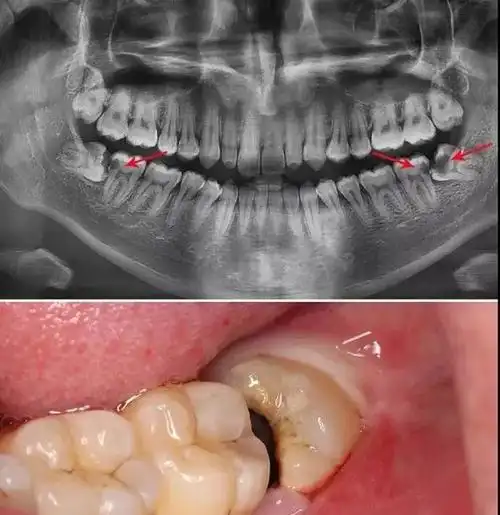

阻生齿最常见于下颌第三磨牙,俗称智齿,此牙萌出年龄在18岁前后,由于

智齿,又叫第三磨牙,是生长在牙列最末端的牙齿,很多人叫它"尽头牙"

智齿是上下颌后牙第三磨牙,相传是智慧的牙齿,因为智齿通常出现在16

它是口腔内最晚萌出的一颗牙也叫阻生牙或第三磨牙智齿通俗的说法就是

智齿是指人类口腔内,牙槽骨上最里面的上下左右各一的四颗第三磨牙.